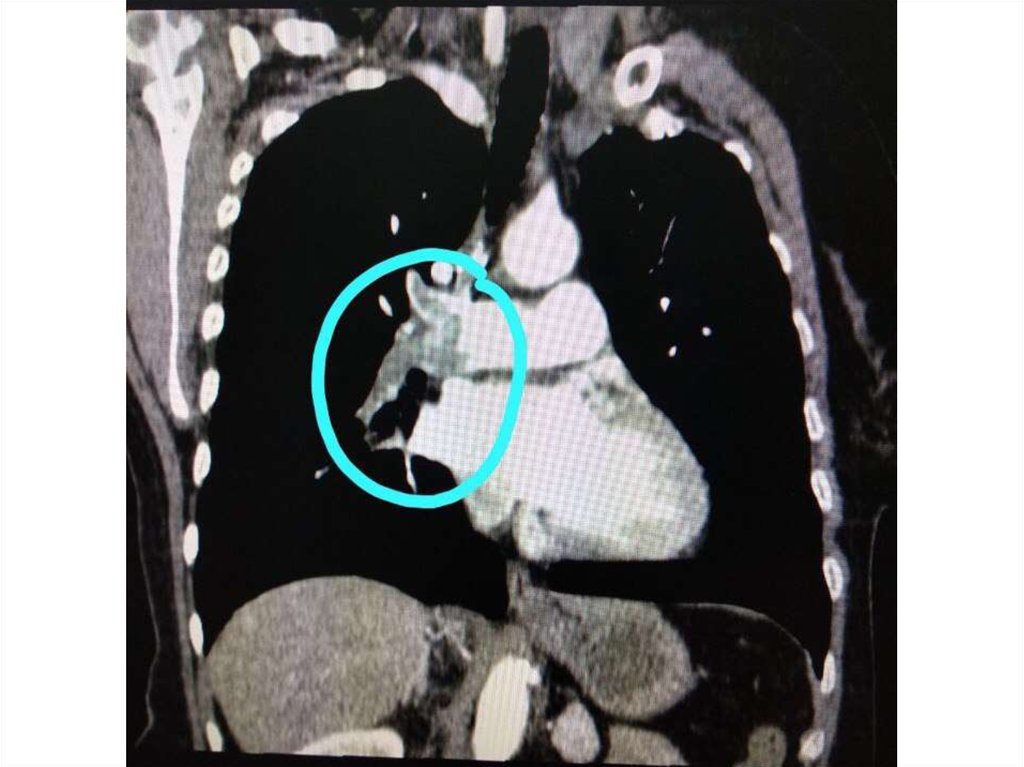

Компьютерная

16.